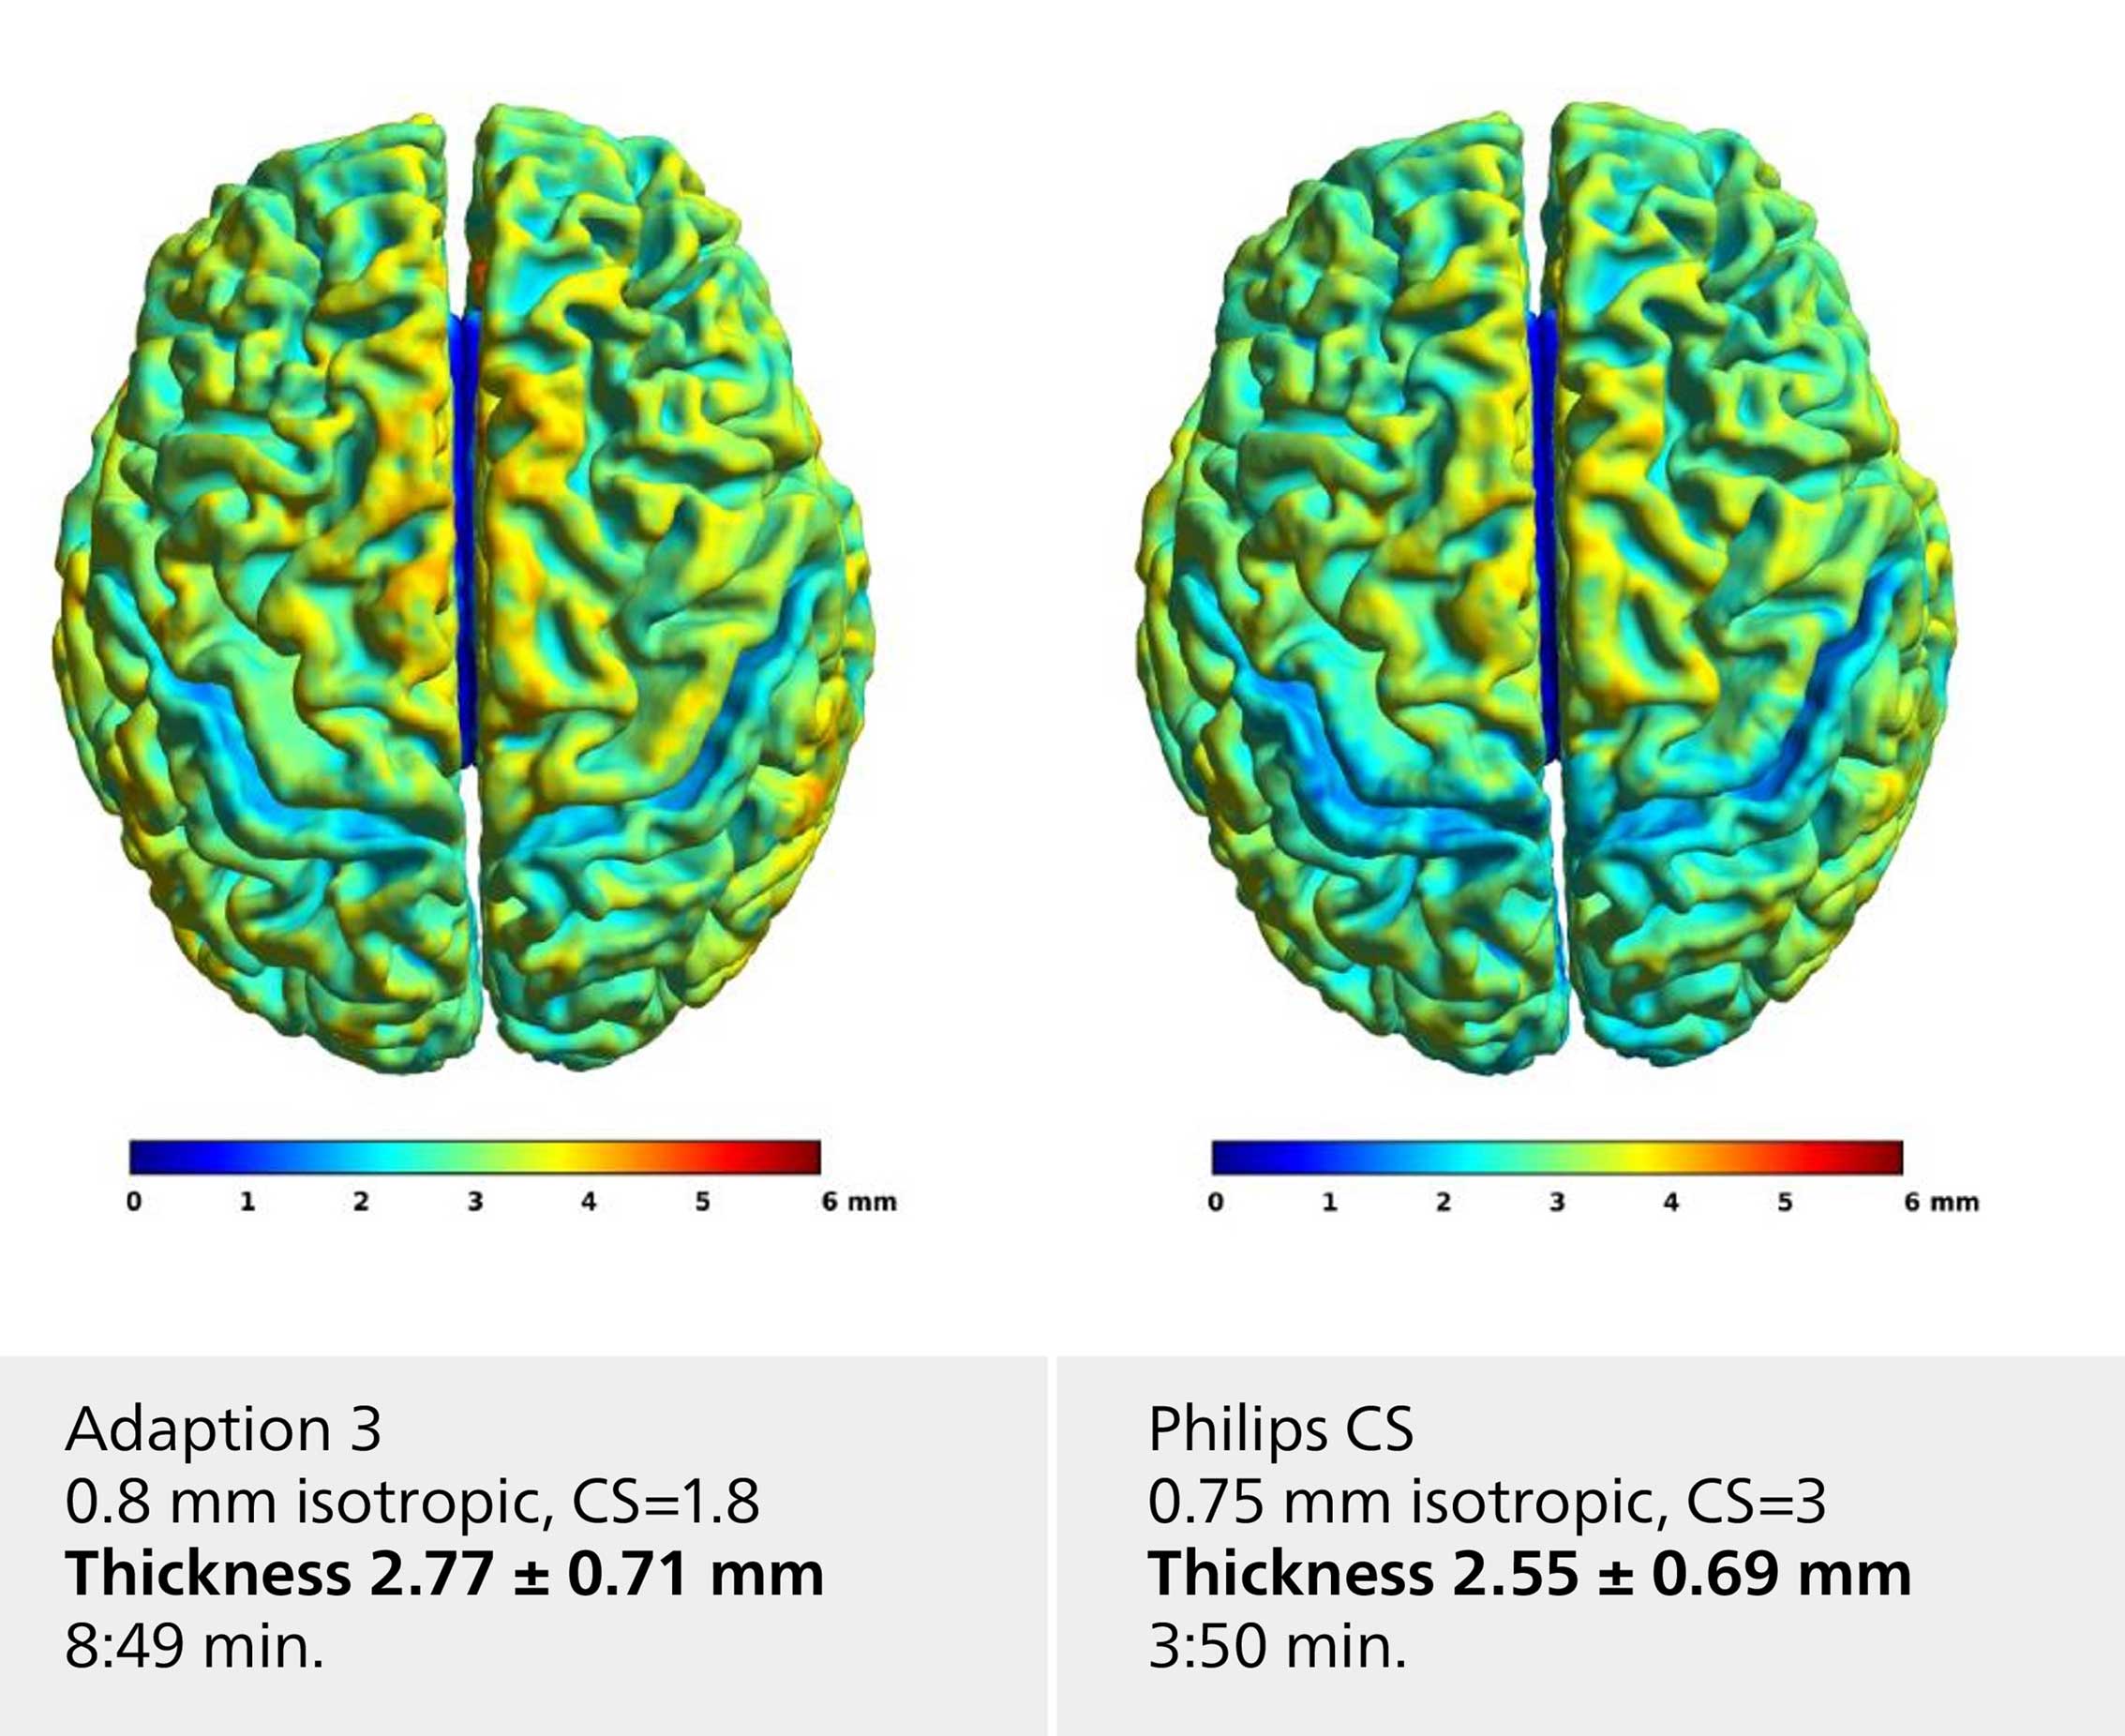

Voxel based morphometry

The neuroscience team compared their standard T1 brain morphometry sequence with alternate protocols facilitating Compressed SENSE. Selected examples shown here include adaption 1 with moderate CS=1.9, higher voxel resolution (0.85 mm), adaption 3 with CS=1.8 and 0.8 mm isotropic voxel size and the Philips protocol database default with CS=3.0 and 0.75 mm isotropic voxel size. All protocols resulted in comparable cortical thickness results with a slight decrease for higher CS-factors.

Voxel based morphometry

The neuroscience team compared their standard T1 brain morphometry sequence with alternate protocols facilitating Compressed SENSE. Selected examples shown here include adaption 1 with moderate CS=1.9, higher voxel resolution (0.85 mm), adaption 3 with CS=1.8 and 0.8 mm isotropic voxel size and the Philips protocol database default with CS=3.0 and 0.75 mm isotropic voxel size. All protocols resulted in comparable cortical thickness results with a slight decrease for higher CS-factors.